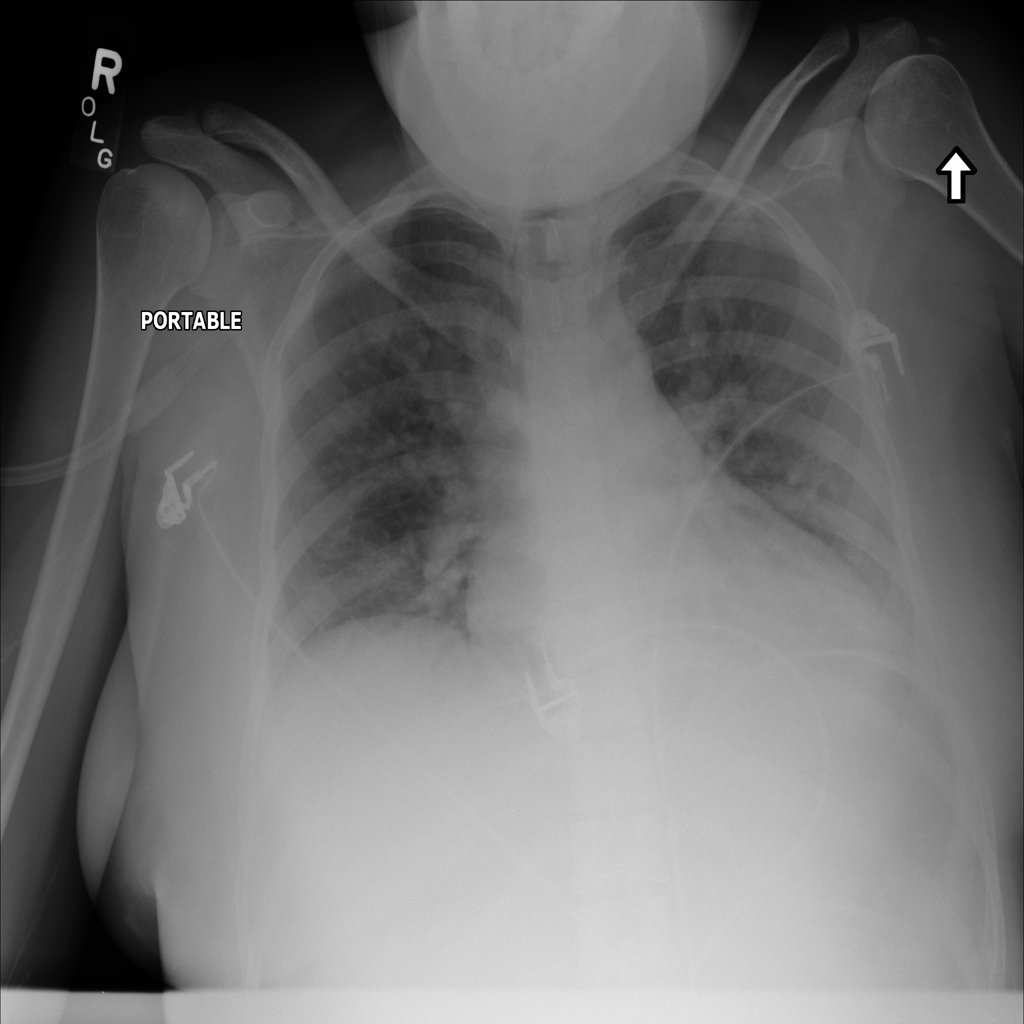

PAT-5B86 · IMG-009Edema

PAT-5B86 · IMG-009

PA